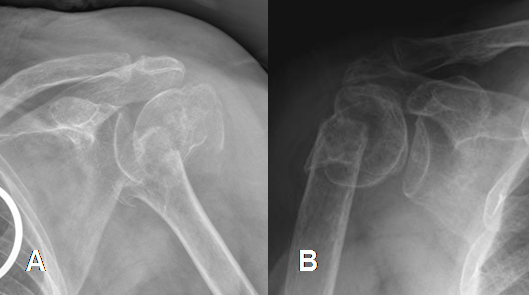

Fig 39. Fractura de húmero.

A y B: Rx AP. Fracturas impactadas y con diferente grado de desplazamiento de la cabeza humeral.